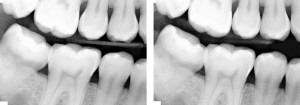

Dental care is the most common unmet health need. Oral disease can severely affect systemic health.

Poor oral health is so important and commonplace:

- dental cavities are the most common chronic disease of childhood (5 times more common than asthma) and

- affects 50% of low-income children.